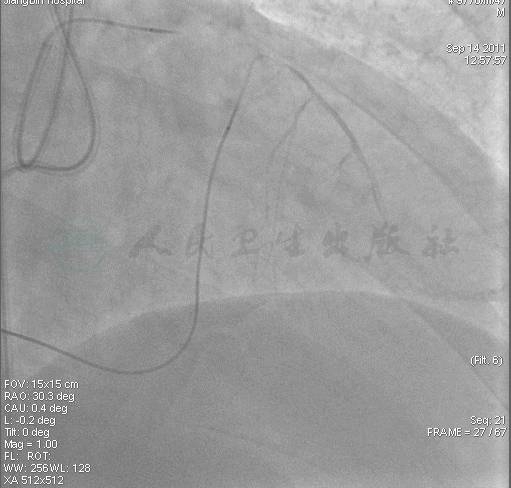

图7 2个月后再次尝试正向失败

图8 2个月后再次尝试正向失败